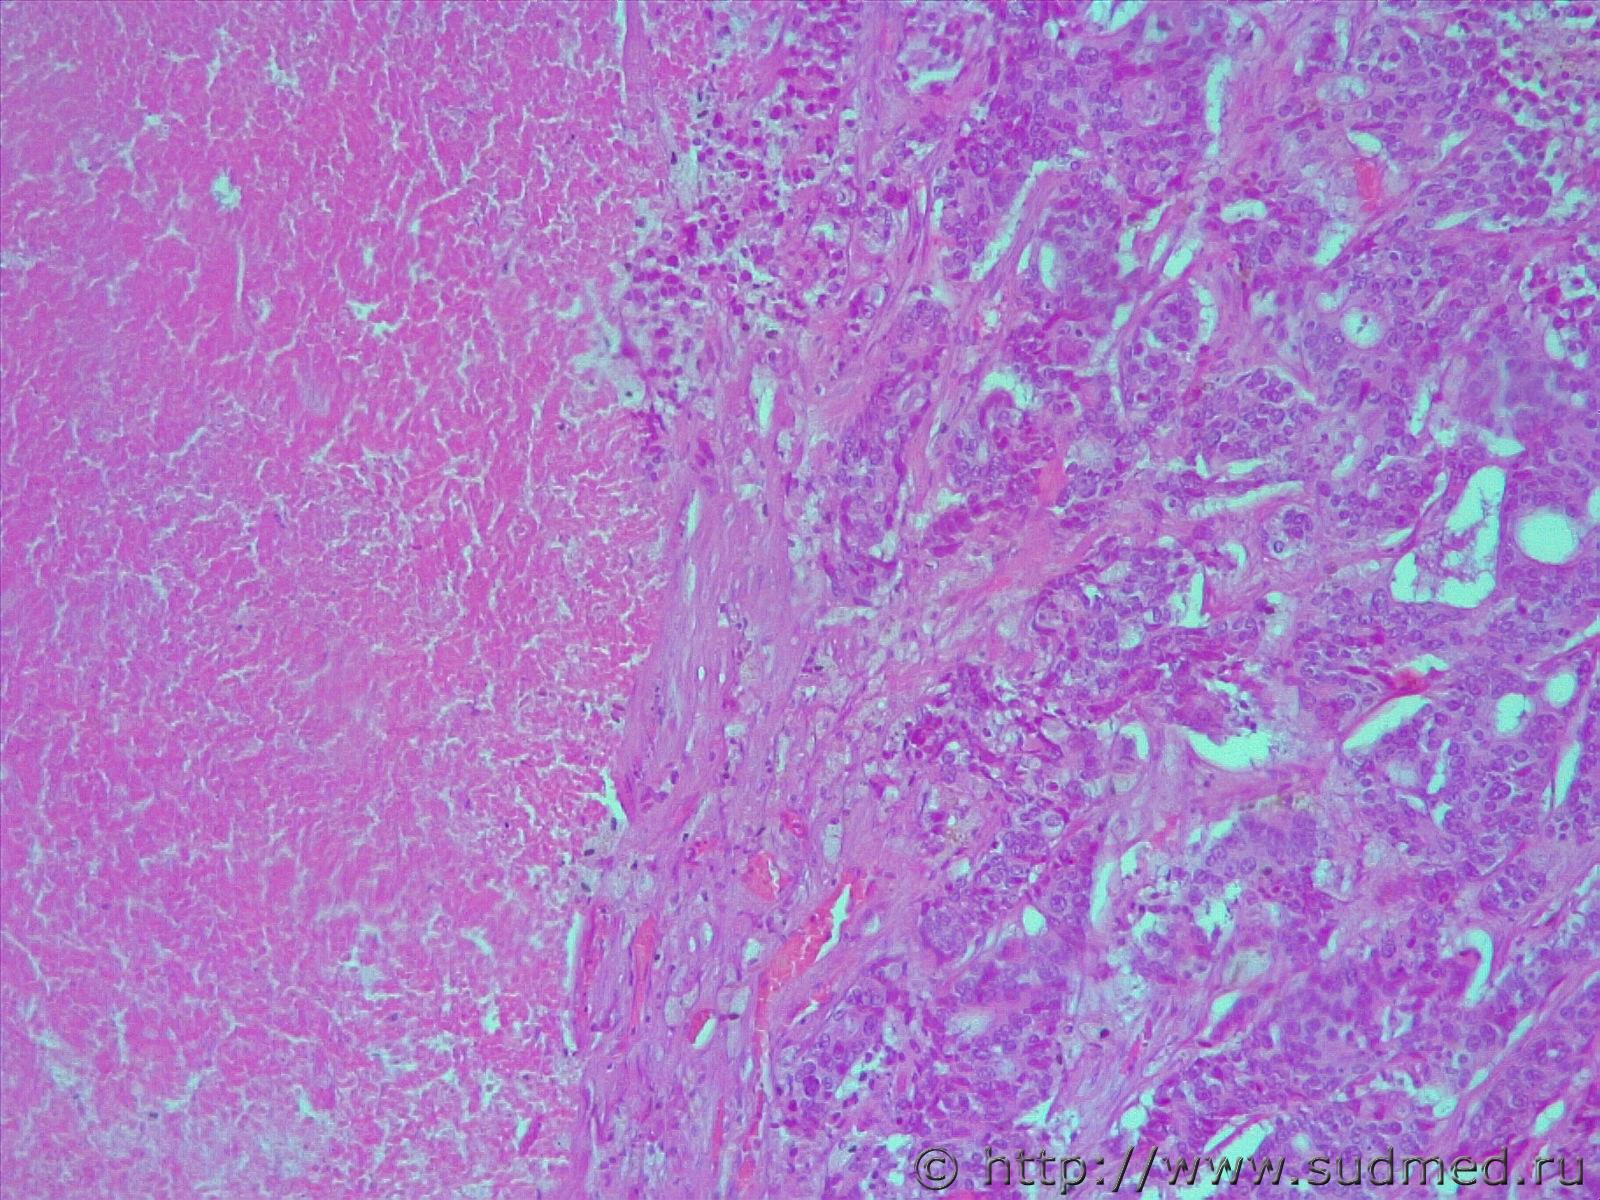

опухоль печени с метастазами в головной мозг, легкие

Напоминает холангиокарциному

Если две темы созданы по одной экспертизе, то метастаз аденокарциномы лёгкого в печень можно спутать с внутрипечёночной холангиокарциномой. Может быть и наоборот. wink.gif

Холангиокарцинома ,но нужна ИГХ верификация